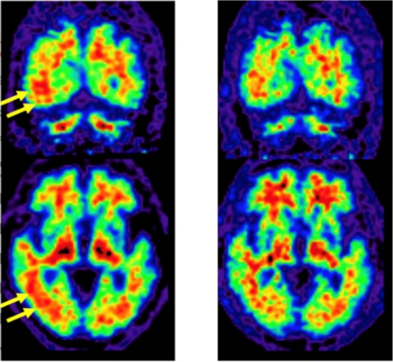

また、これまで脳アミロイドPET検査においては、灰白質への集積が曖昧で、判定に苦慮する症例が約1割あるといわれてきました。今回の検証では、17例中1例の患者において、従来型PET/CT装置で、右側頭葉にアミロイド沈着が確認されました。読影指針※8 に従えば、アミロイド沈着陽性(アルツハイマー病理が存在する)と診断されるものです。しかし、本PET装置による画像では、右側頭葉を含めたどの部位にもアミロイド沈着はなく、陰性と判定され、診断が変更されることになりました。

左:従来PEF/CT装置により得られた脳アミロイドPET画像

黄色矢印の部分で灰白質にアミロイドの分布を示すPET薬剤集積がひろがっているようにみえ(赤い部分が脳の表面までひろがっている)、同部にアミロイドが蓄積していると判定された。

右:本装置により得られた脳アミロイドPET画像

従来PET/CT装置でアミロイド蓄積陽性と判定された部分について、灰白質まで集積が及んでいないことが明白である(赤い部分は脳の表面まで達していない)。